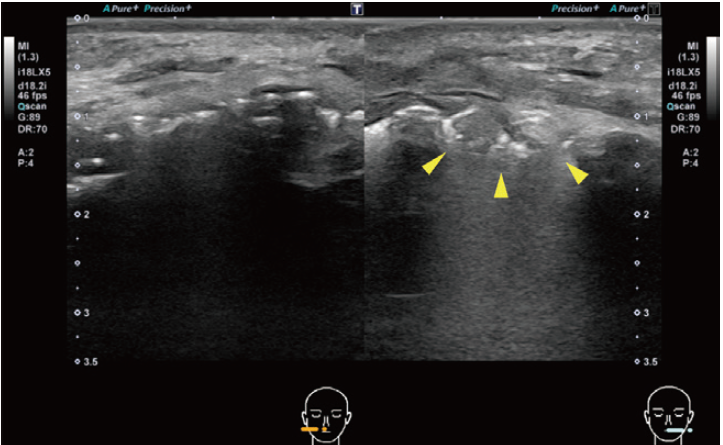

画像所見:US所見;左頰粘膜は対側に比してわずかに腫脹がみられた(図2)。